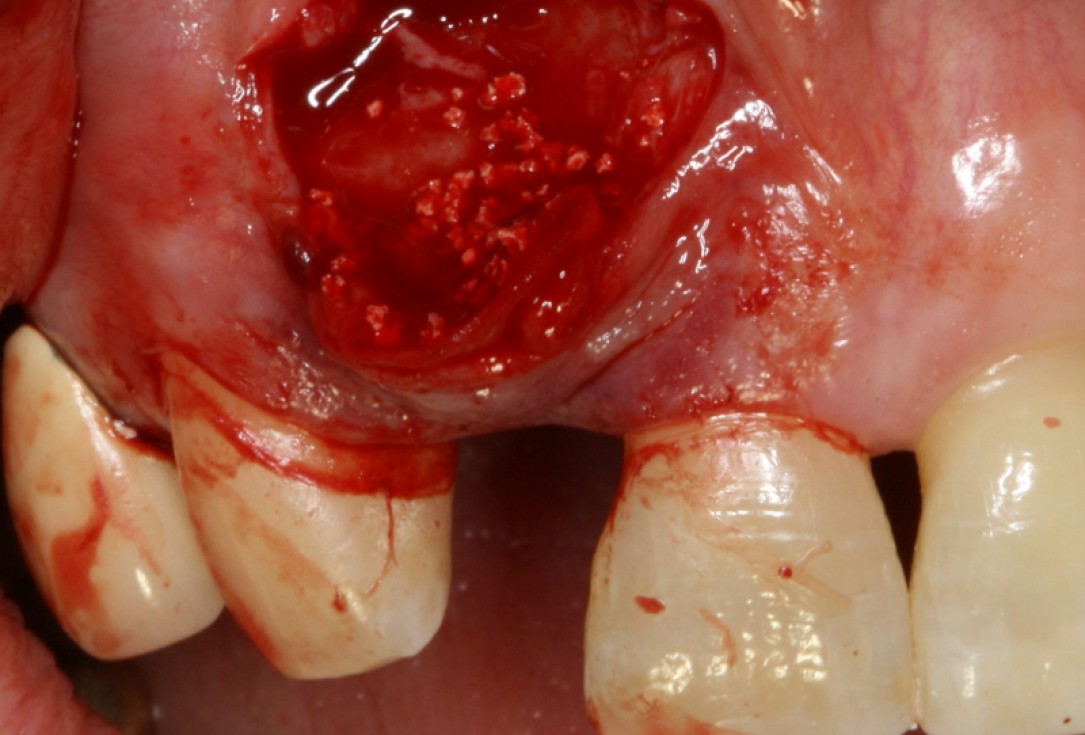

02/20 - Clinical situation before surgeryGBR with maxresorb® & Jason® membrane - Prof. Dr. Dr. D. Rothamel

07/20 - Second surgical site: clinical situation preoperativelyGBR with maxresorb® & Jason® membrane - Prof. Dr. Dr. D. Rothamel

Clinical situation before extraction